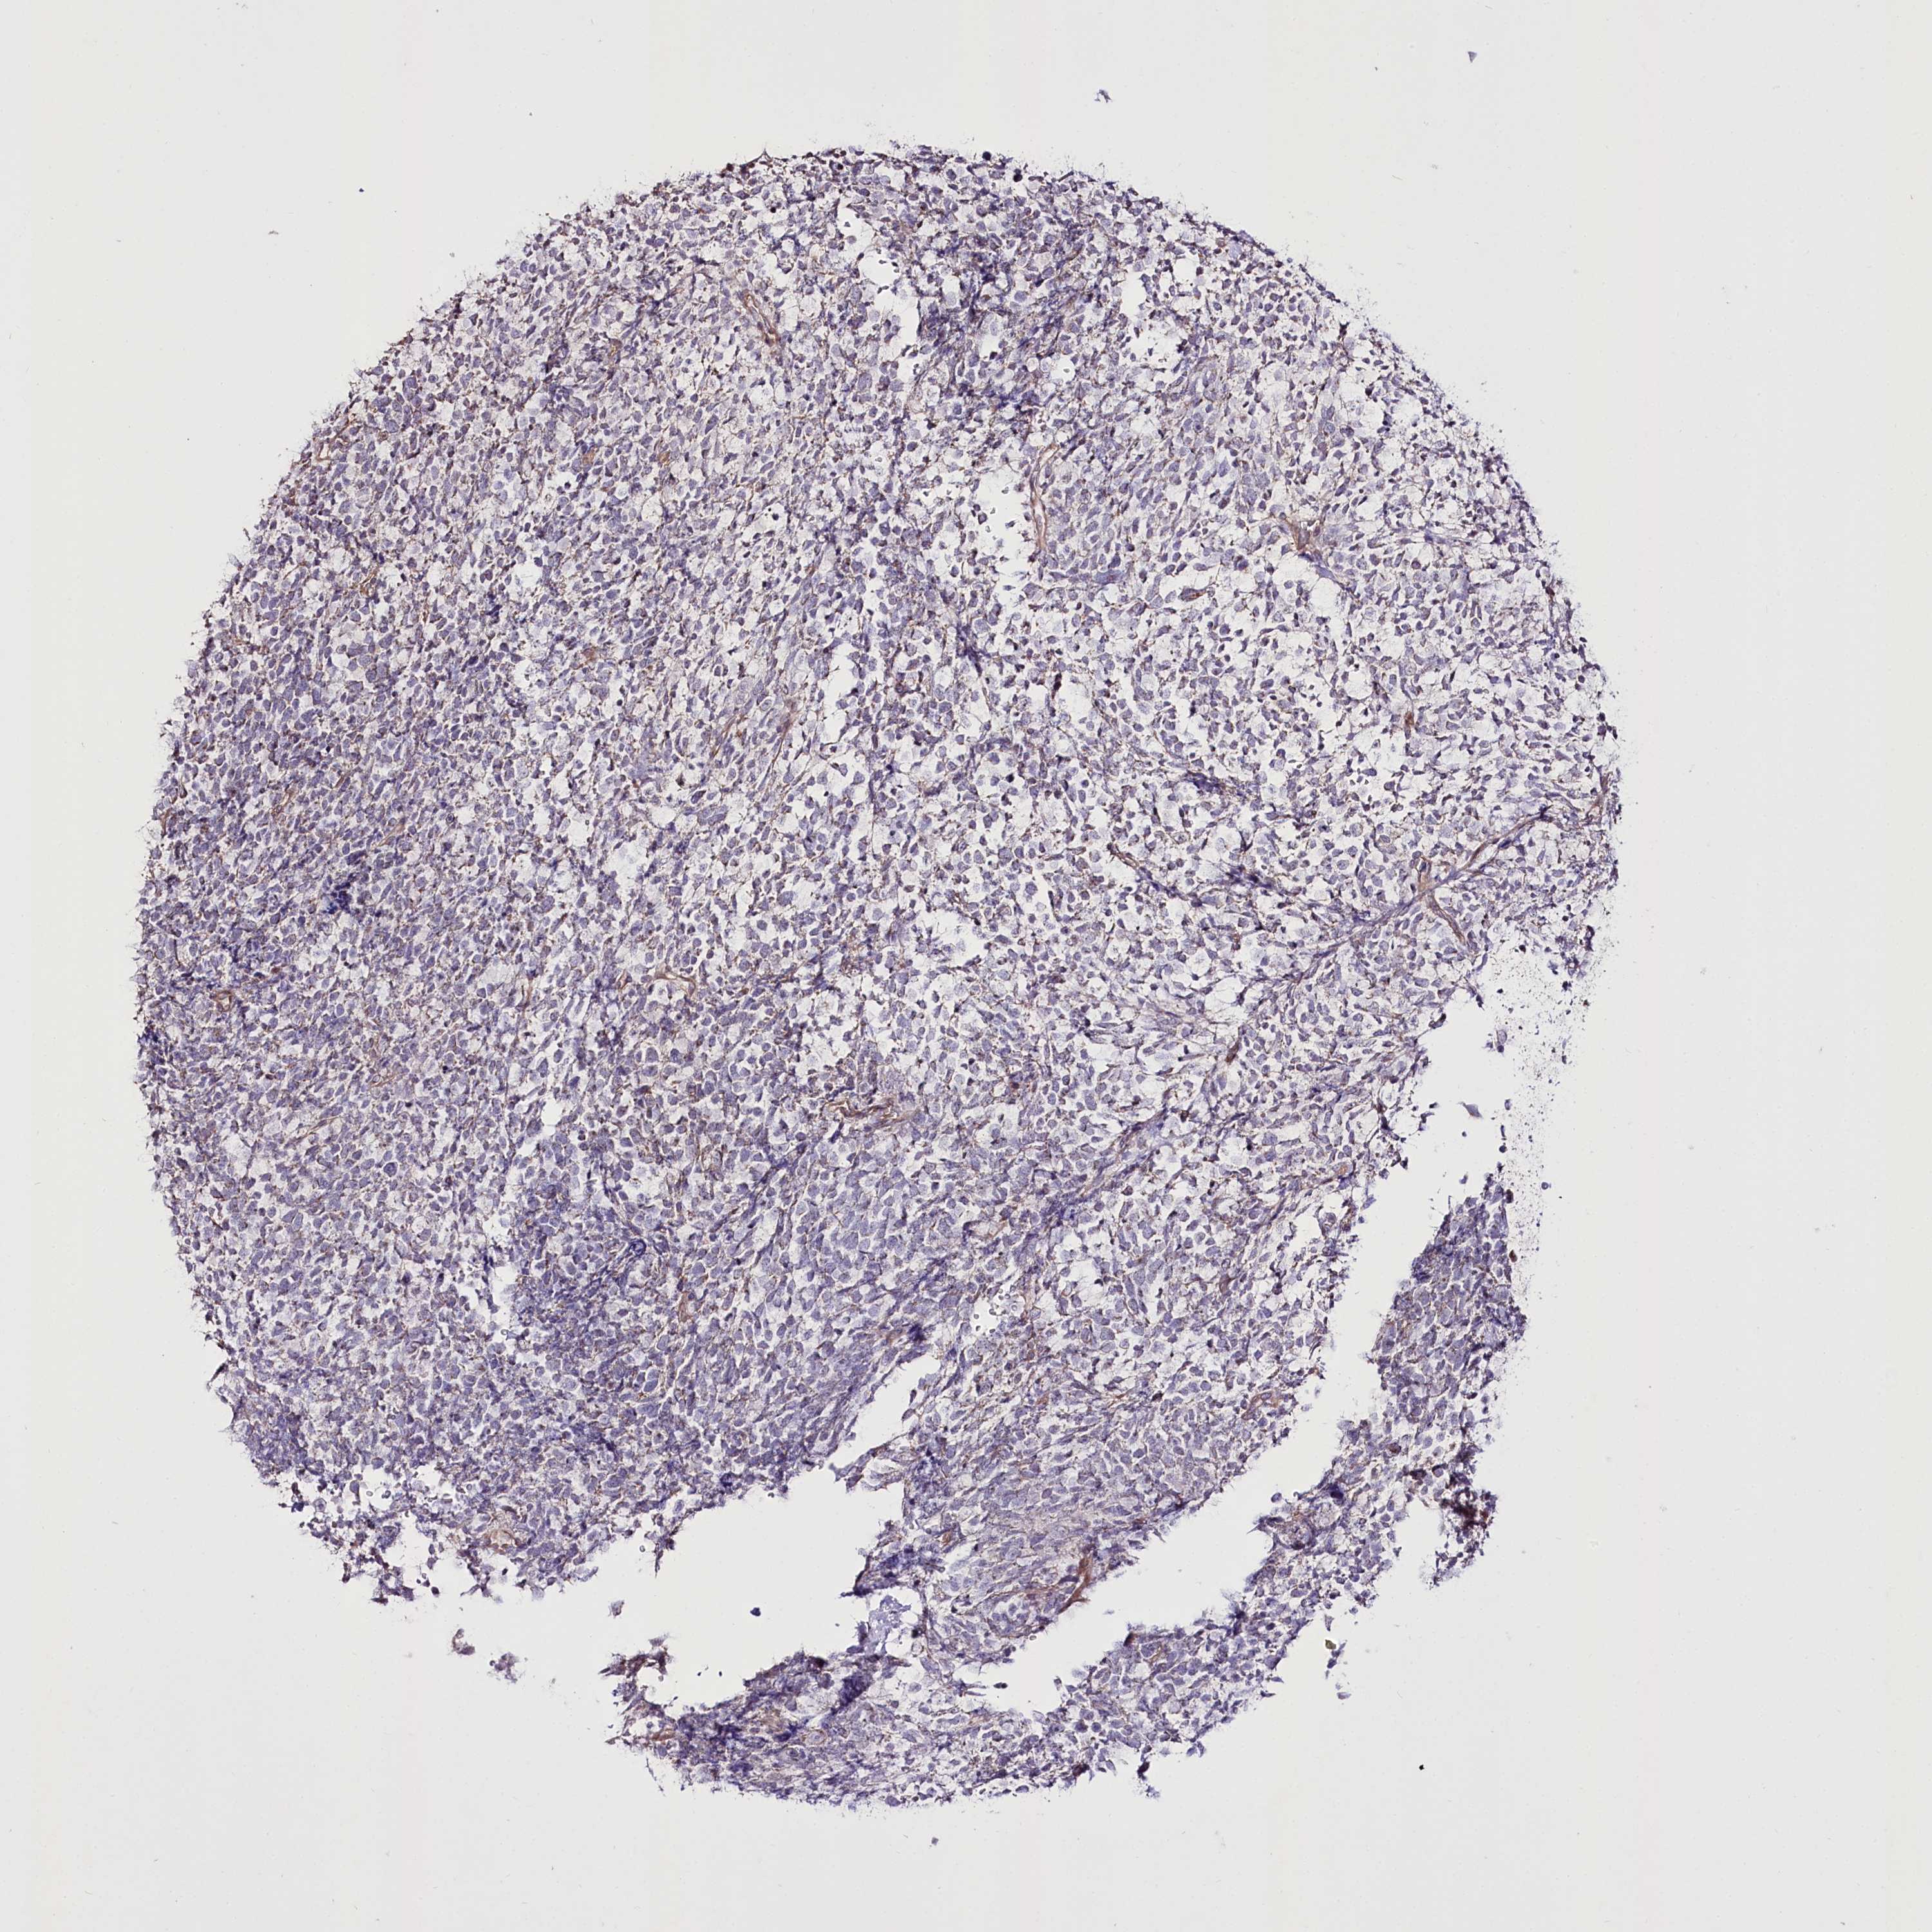

UROTHELIAL CANCER - Protein expressioni

A mouse-over function shows sample information and annotation data. Click on an image to view it in a full screen mode. Samples can be filtered based on level of antibody staining by selecting one or several of the following categories: high, medium, low and not detected. The assay and annotation is described here.

Note that samples used for immunohistochemistry by the Human Protein Atlas do not correspond to samples in the TCGA dataset.

Antibody stainingi

Antibody staining in the annotated cell types in the current human tissue is reported as not detected, low, medium, or high, based on conventional immunohistochemistry profiling in selected tissues. This score is based on the combination of the staining intensity and fraction of stained cells.

Each image is clickable and will lead to virtual microscopy that enables deeper exploration of all samples and also displays staining intensity scores, fraction scores and subcellular localization as well as patient and tissue information for each sample.

Antibody HPA038450

Antibody HPA038451

Staining

High

Medium

Low

Not detected

Intensity

Strong

Moderate

Weak

Negative

Quantity

>75%

75%-25%

<25%

None

Location

Nuclear

Cytoplasmic/membranous

Cytoplasmic/membranous,nuclear

Urothelial carcinoma, High grade

Urothelial carcinoma, Low grade

Urothelial carcinoma, NOS